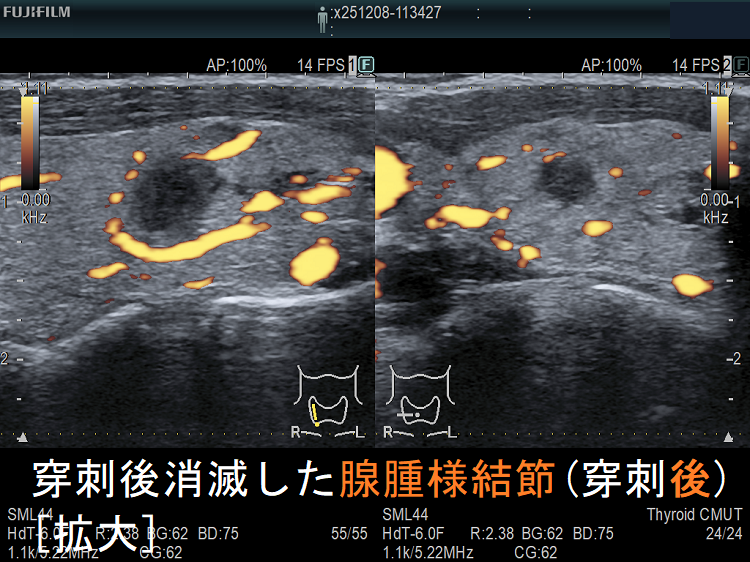

穿刺細胞診後内部融解

![穿刺後消滅した腺腫様結節(穿刺後)ドプラーモード[拡大] 穿刺後消滅した腺腫様結節(穿刺後)ドプラーモード[拡大]](../images/basic/basic5/images20251216212330.png)